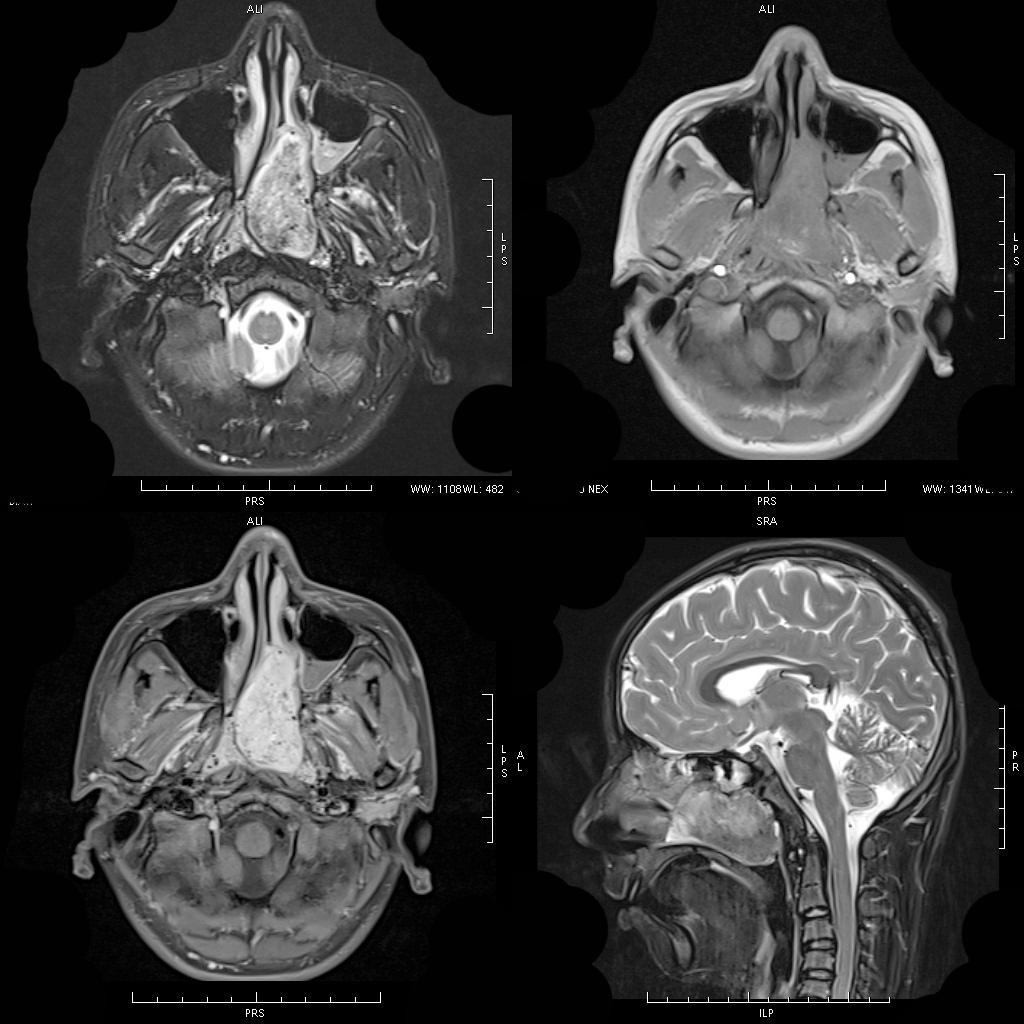

MRI 表现:鼻咽后壁及两侧壁不规则软组织肿块,信号多较均匀,T1WI 像呈等信号,T2WI 像呈稍高信号,DWI 像为明显高信号。增强扫描肿块常轻-中度均匀强化,液化坏死少见。颈部淋巴结肿大常见。肿大淋巴结多边缘规则,内部密度或信号均匀,增强扫描轻度强化。对邻近组织侵犯少,肿块与咽后壁头长肌等分界清楚,多无颅底及相邻骨质破坏。鼻咽部肿块虽较明显,但咽旁间隙较清晰,或只有受压改变。

MRI 表现:早期表现为鼻咽顶后壁轻度软组织增厚、突起,表面不规则、边界不清;咽隐窝变浅甚至消失,鼻咽轮廓改变,双侧结构不对称;进展期肿瘤增大向周围组织、结构浸润生长,并可破坏颅底骨质结构,以中线部蝶骨体和枕骨斜坡最常见。肿瘤在 T1WI 像上呈中等或中低信号,T2WI 像上呈中等或中高信号,边缘模糊呈浸润状;增强扫描多呈明显强化,肿块内坏死区无强化。颈部较小的转移淋巴结边缘多较清楚、信号均匀;较大的淋巴结中央常见液化坏死,多发增大的淋巴结可融合呈巨大的肿块,信号不均匀。